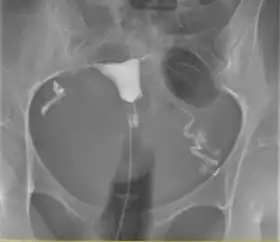

![]() A normal hysterosalpingogram. Note the catheter entering at the bottom of the screen, and the contrast medium filling the uterine cavity (small triangle in the center). | |

Hysterosalpingography (HSG), also known as uterosalpingography,[1] is a radiologic procedure to investigate the shape of the uterine cavity and the shape and patency of the fallopian tubes. It is a special x-ray procedure using dye to look at the womb (uterus) and fallopian tubes.[2] In this procedure, a radio-opaque material is injected into the cervical canal, and radiographs are taken. A normal result shows the filling of the uterine cavity and the bilateral filling of the fallopian tube with the injection material. To demonstrate tubal patency, spillage of the material into the peritoneal cavity needs to be observed. Hysterosalpingography has vital role in treatment of infertility, especially in the case of fallopian tube blockage.